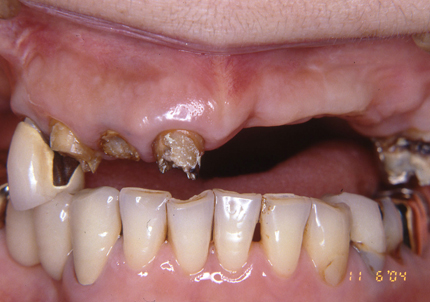

2.上顎補綴物除去

3.上顎補綴物除去、旧インプラント除去手術後(骨吸収後)

4.前歯部骨造成(G.B.R)

➡G.B.Rとは?

インプラント治療において、骨の厚みや高さが不足している場合に、骨を増やしてインプラントを安定させるための骨造成手術です。具体的には、自家骨や人工骨を充填し、特殊な膜で覆うことで、骨の再生を誘導します。

5.仮歯装着歯装着